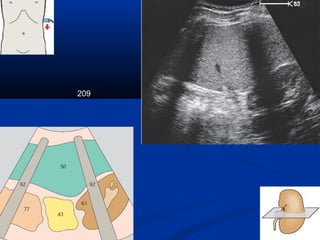

Kyõ thuaät : caùc maët caétKyõ thuaät : caùc maët caét

209